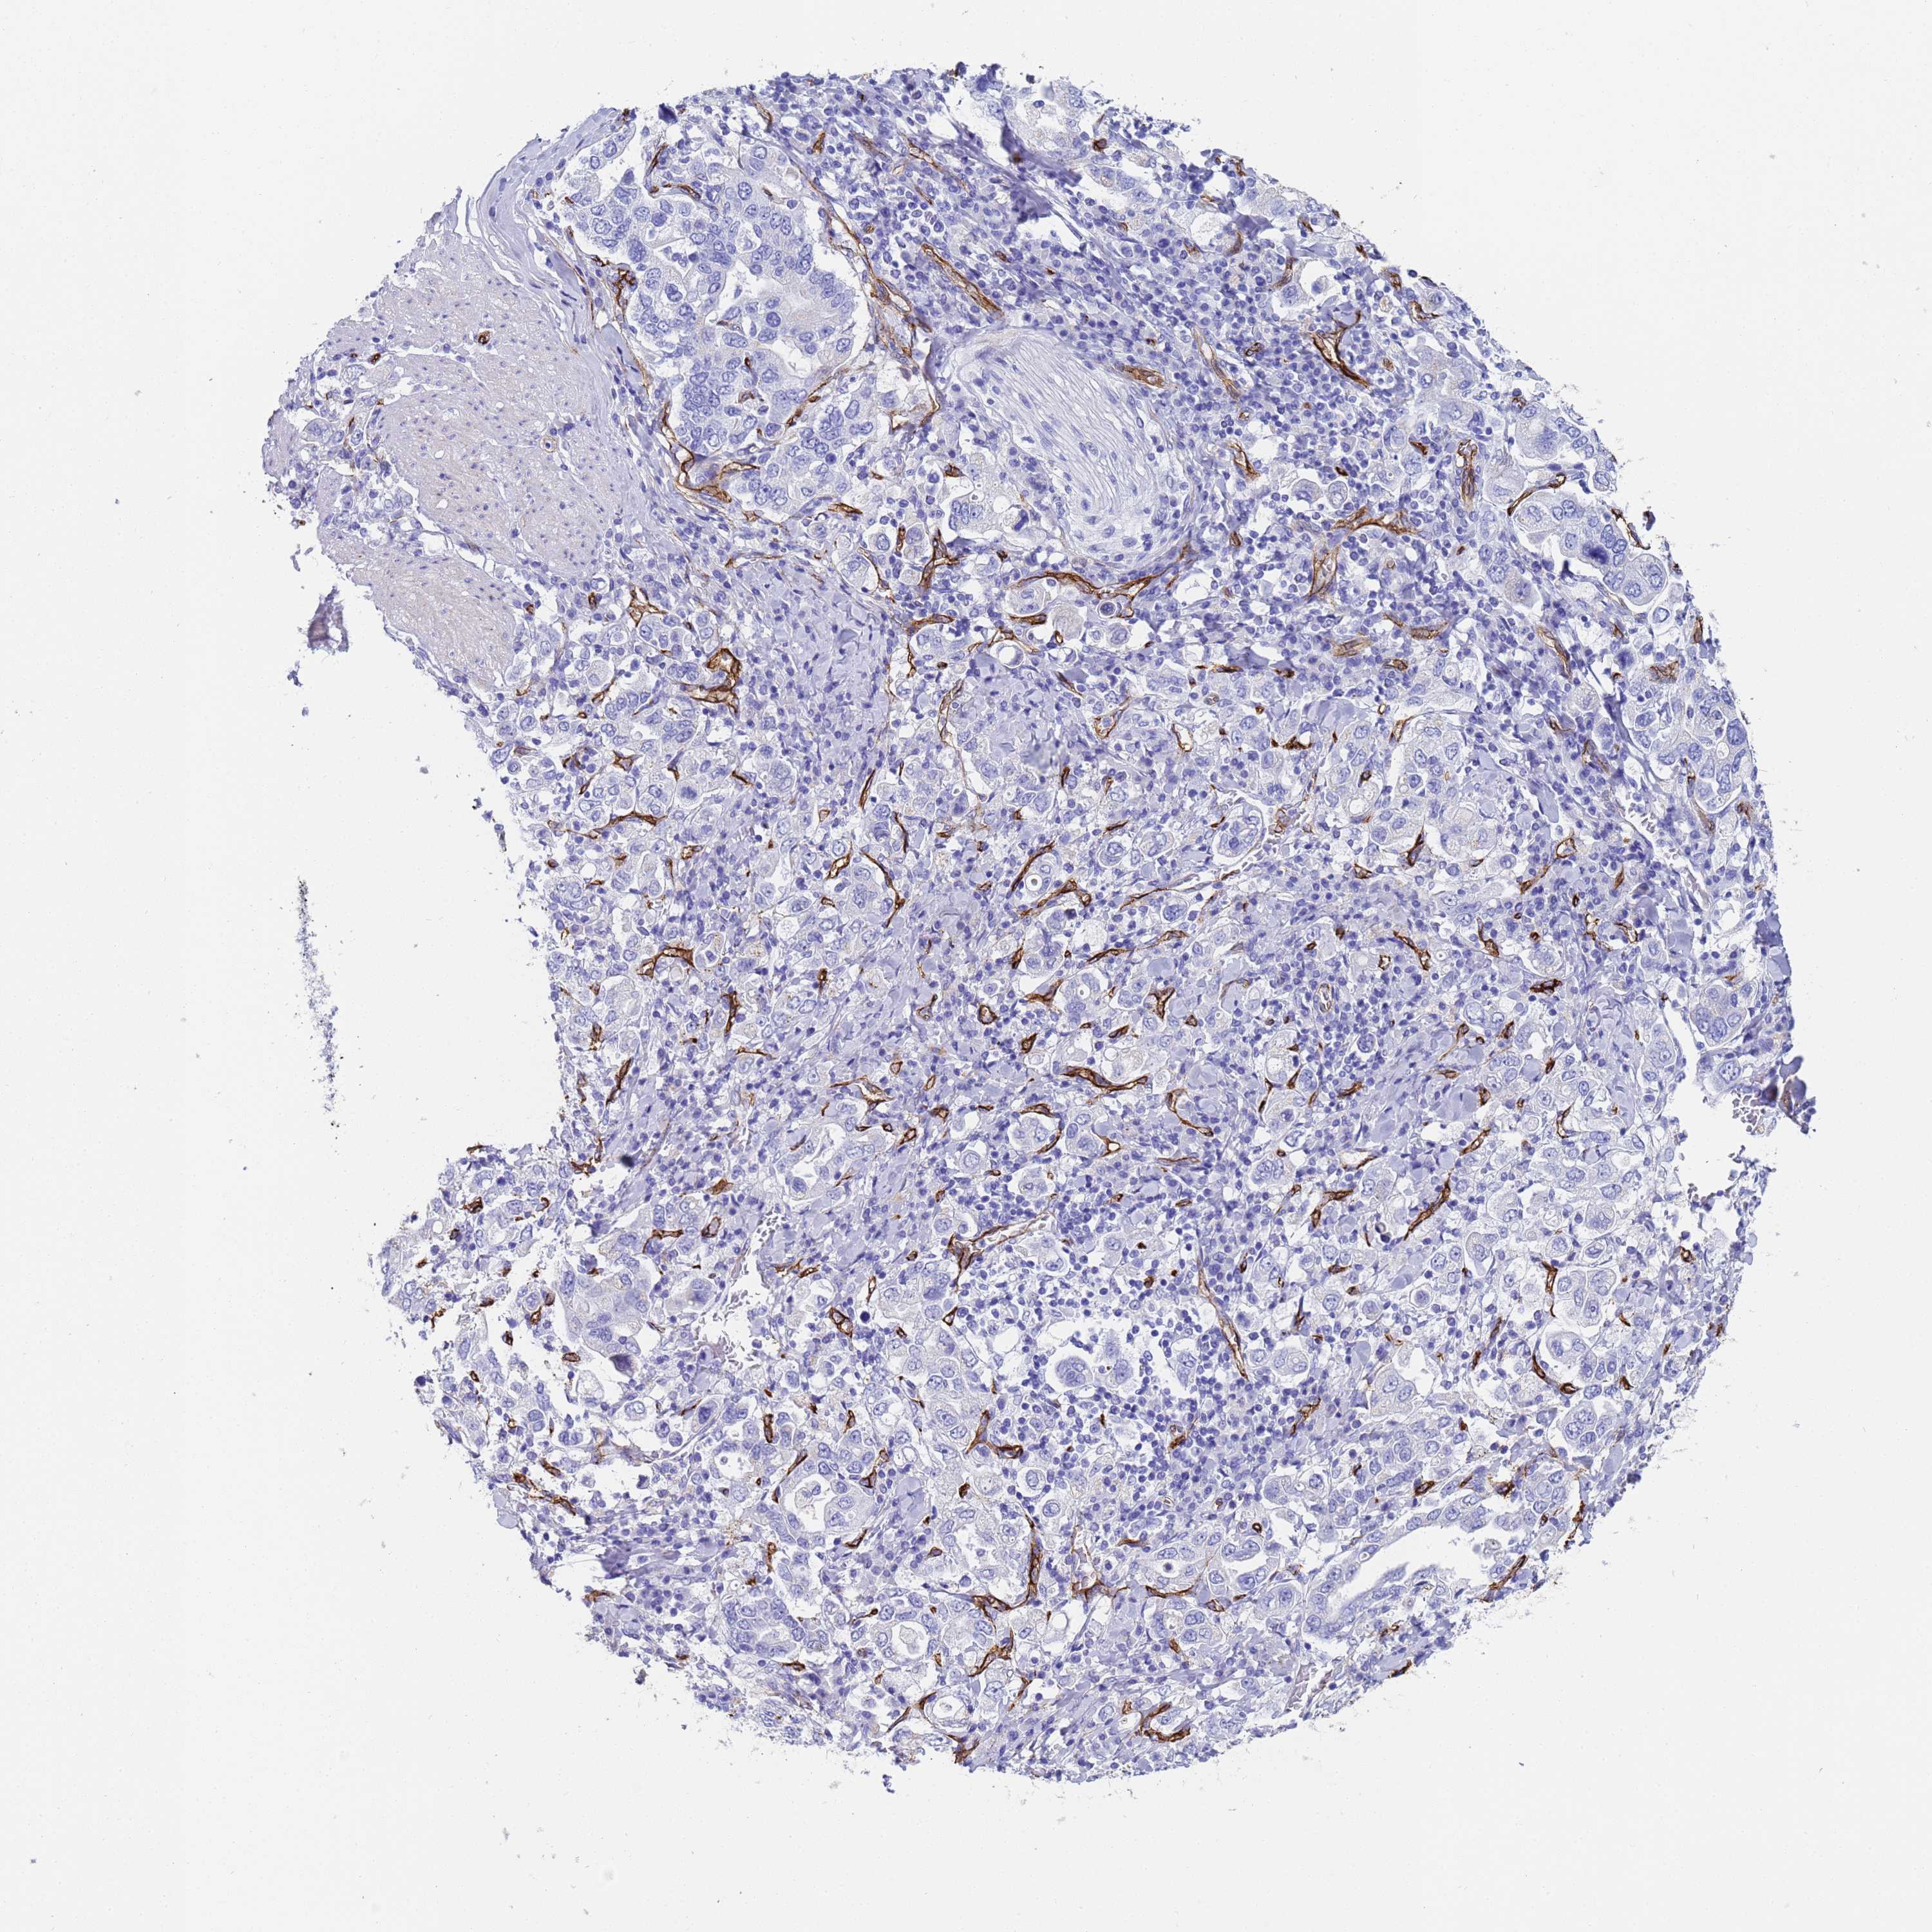

STOMACH CANCER - Protein expressioni

A mouse-over function shows sample information and annotation data. Click on an image to view it in a full screen mode. Samples can be filtered based on level of antibody staining by selecting one or several of the following categories: high, medium, low and not detected. The assay and annotation is described here.

Note that samples used for immunohistochemistry by the Human Protein Atlas do not correspond to samples in the TCGA dataset.

Antibody stainingi

Antibody staining in the annotated cell types in the current human tissue is reported as not detected, low, medium, or high, based on conventional immunohistochemistry profiling in selected tissues. This score is based on the combination of the staining intensity and fraction of stained cells.

Each image is clickable and will lead to virtual microscopy that enables deeper exploration of all samples and also displays staining intensity scores, fraction scores and subcellular localization as well as patient and tissue information for each sample.

Antibody HPA051767

Antibody CAB046467

Staining

High

Medium

Low

Not detected

Intensity

Strong

Moderate

Weak

Negative

Quantity

>75%

75%-25%

<25%

None

Location

Nuclear

Cytoplasmic/membranous

Cytoplasmic/membranous,nuclear

Adenocarcinoma, NOS